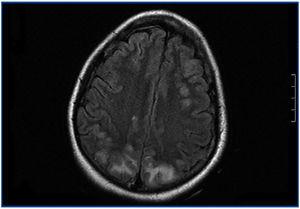

En el período interdiálisis presenta malestar general, desorientación temporal y nivel de conciencia fluctuante. Es trasladada al Servicio de Urgencias, donde presenta dos crisis convulsivas tónico-clónicas generalizadas, que ceden con benzodiazepinas, con recuperación del nivel de conciencia entre las crisis. En la exploración física se muestra afebril, con tensión arterial (TA): 151/108, apertura ocular espontánea, respuesta verbal correcta. Pupilas isocóricas y normorreactivas. Pares craneales normales; fuerza y sensibilidad conservada en las cuatro extremidades. Signos meníngeos negativos. No presenta otros hallazgos de interés. Se realiza radiografía de tórax y tomografía computarizada craneal, sin hallazgos. Ante una tercera crisis y el empeoramiento progresivo de su estado general, ingresa en la Unidad de Cuidados Intensivos, donde precisa sedación, intubación orotraqueal y ventilación mecánica inducida (VMI). En la analítica destaca leucocitosis con desviación izquierda, acidosis láctica severa, negatividad de anticuerpos antimembrana basal, anticuerpos antinucleares, anticuerpos anticitoplásmicos de neutrófilos, inmunocomplejos, anti-DNA, anti-SS-A. anti-SS-B, anti-RNP, anti-Scl-70, con complemento e inmunoglobulinas normales. Hemocultivos y urocultivos negativos. Estabilidad iónica. Fibrobroncoscopia sin hallazgos. Punción lumbar normal. Cultivo de líquido cefalorraquídeo para bacterias, hongos y virus negativo. Electroencefalograma con ritmo basal lento en rango delta con ondas de actividad theta de predominio en regiones temporales bilaterales. Dos descargas epileptiformes en zona parietal derecha. Resonancia magnética nuclear (RMN) craneal con hiperintensidad de señal en secuencias potenciadas en T2 y FLAIR, sugerente de edema vasogénico, de localización corticosubcortical en las porciones posteriores de ambos lóbulos parietales, occipitales y frontal derecho que en la secuencia de difusión no muestra restricción significativa (figura 1). Ante estos hallazgos, se llega al diagnóstico de SLPR. Se inicia tratamiento con fenitoína, antibioterapia empírica y hemodiafiltración venovenosa continua. Mantiene severa HTA que precisa tratamiento con 6 fármacos (captopril, amlodipino, doxazosina, atenolol, nitroglicerina y urapidilo). En los siguientes días, mejora, sin recurrencia de las crisis y manteniendo TA correctas, por lo que se puede retirar la VMI y puede ser dada de alta a los 18 días de ingreso, con atenolol y captopril como tratamiento de base.

Figura 1. Resonancia magnética nuclear craneal